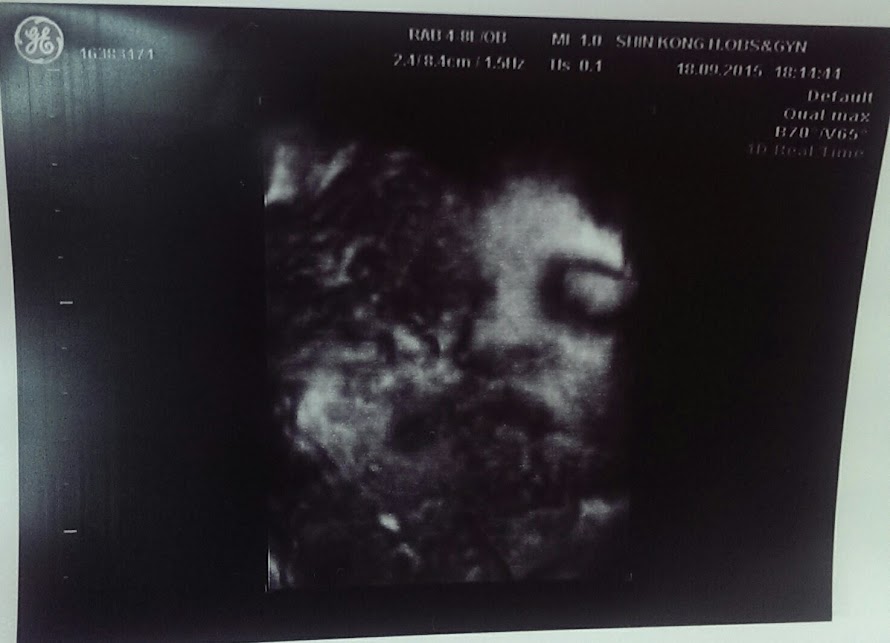

小瑰出發前還特別準備義美布丁,想要驗完尿在等待超音波的時候用布丁把毛毛喚醒,殊不知又是一個人算不如天算,因為在診間看完診之後,小瑰連超音波的椅子都沒碰到,就直接進去超音波室了,所以睡美人毛毛依然在睡覺XD

而且還貼著胎盤在睡覺~